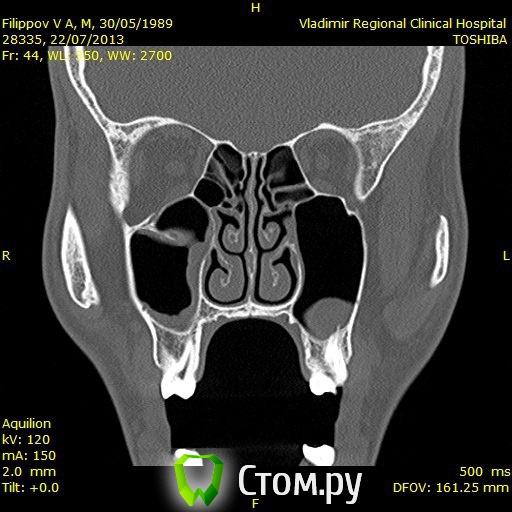

Доброго времени суток,помогите пожалуйстабеспокоит заложенность носа уже 3ий год,обший ослабленный иммунитет что выражается в частых простудах,возраст 25 лет,причина этого гдето в зубах,так как кроме этого проблем небыло никогда,когда начились эти проблему начал ходить к стомалогам мне сделали порядка 7 пломб,в одном был пульпит,как пульпит переличили стало легче но не до конца ,затем на мскт увидели кисту под депульпированной 7кой,

вот зуб пролечил у ильи мера,в 2 этапа,первый раз он сделал,и залили лекарство и сказал зуб врядли сохраним,через месяц второй прием все доделал и сказал что все хорошо,после этого общее состояние стало хуже,возможно из-за того что врач сказал что все с пульпы сливалось прямо в пазуху, вот это делали в марте ,после этого сделал мскт киста с зуба увеличилась с 1см до 1,5см, я лег в больничку местную и мнее ее вырезали,после этого прошел 1 месяц улучшений нет все также заложенность в носе и пониженный иммунитет,не подскажите что делать?кисту просто вырезали резекцую корня зуба не делали вот снимки до вырезания кисты после первого раза лечения каналов